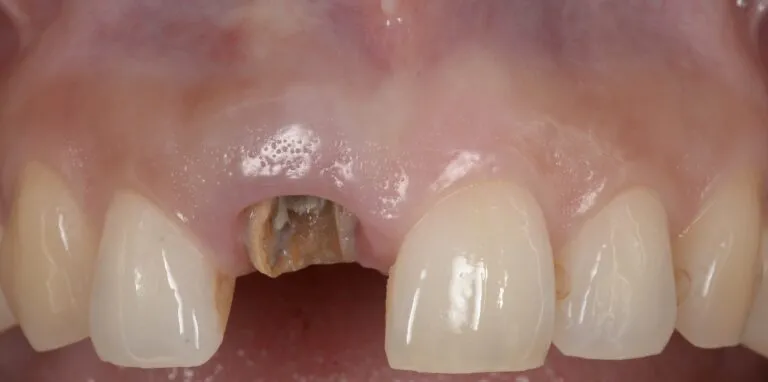

症例1

- 主訴

- 前歯が折れたのでインプラント治療希望

- 治療内容

- 右上中切歯に抜歯即時でインプラントを埋入

- 治療費

- 45万円

- 治療期間

- 4ヶ月

- 通院回数

- 8回

- 想定されたリスク

- インプラント部の歯茎が退縮してしまう

- コメント

- 抜歯即時埋入で行った為、外科処置は一回のみで、審美的に治療を終えることができた

before

after